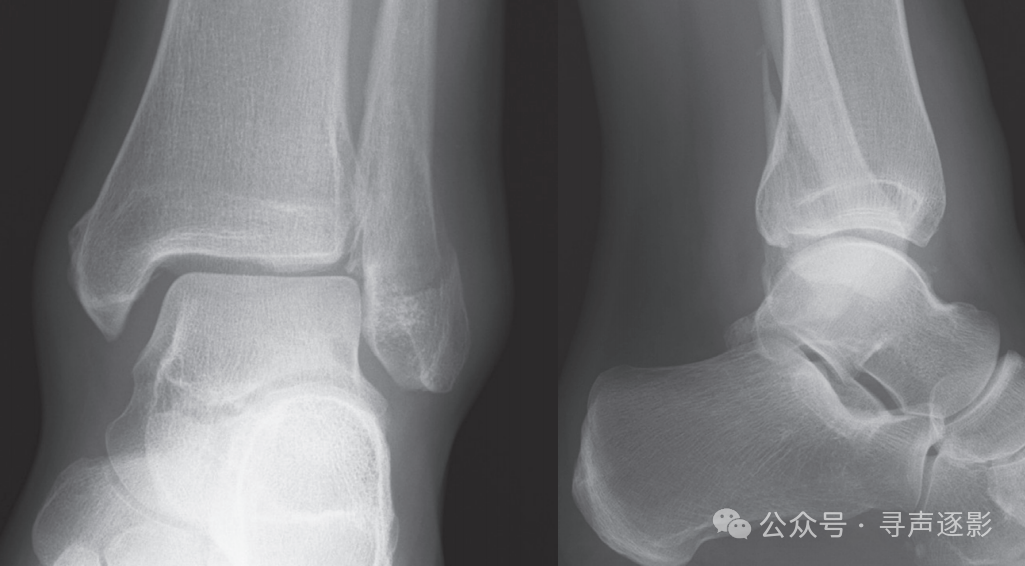

正常踝关节(左,成人;右,儿童)正位 Mortise片

正常踝关节侧位片